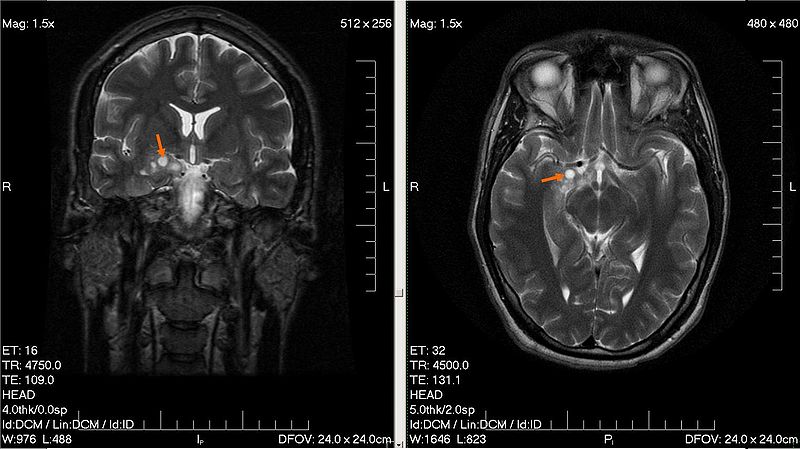

- Radiopaedia